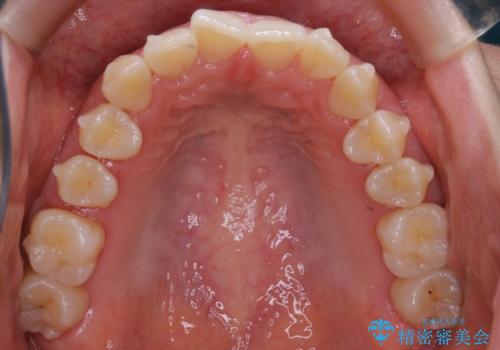

初診時の写真では一見噛み合わせには問題がないように見えても、実際に精密な検査を行うと改善すべき点が見つかる場合も多くあります。

当院では、矯正治療は見た目の改善が主目的ではなく機能面を改善し自然に長持ちする口腔内環境を整えることに重きを置く必要があると考えます。

しかしながら、こちらの理想だけを押し付けるだけが良い治療とは言えないので、患者様と治療のゴールの設定をよく話し合ったうえで方針を決定していくことが最も重要です。